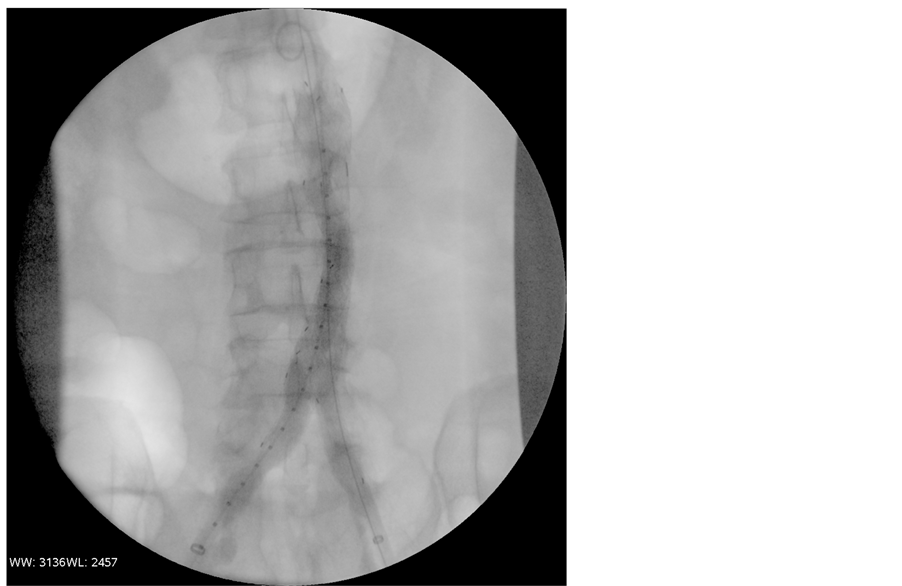

The initial management consisted of anticoagulation with heparin associated with spinal fluid drainage. As the clinical diagnosis was a spinal cord embolization from the aortic aneurysm with an ischemic Cauda equina syndrome, he was deemed to be at risk for further embolization. The patient was transferred to the operating theatre without delay and the aneurysm was repaired with an aortic endograft. The control angiogram showed successful exclusion of the infrarenal aortic aneurysm without evidence of an endoleak or distal embolization. The postoperative CT showed a total exclusion of the AAA without any sign of endoleak (Figure 3).

Figure 3. Per-operative control angiogram showing successful exclusion of the infrarenal aortic aneurysm without any endoleak or distal embolization (EVAR).